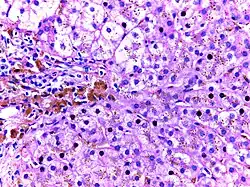

![]() | Macrophages | Lung showing congestion with plenty of alveolar macrophages containing phagocytosed brownish granular hemosiderin pigment. | Category: Macrophages | Macrophage |